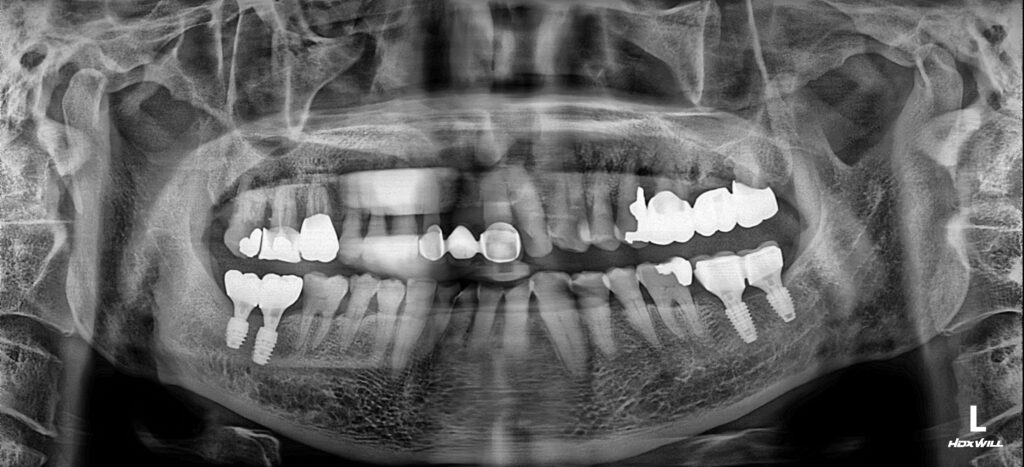

영도임플란트 서울화이트S치과에 처음 내원하셨을 때의 모습입니다. 사진에서 표시된 앞니 브릿지가 흔들린다고 하셨는데요. 오른쪽 작은앞니(사진에서 왼쪽)가 치주질환으로 살리기 어려운 상태였습니다.

서울화이트S치과오른쪽 작은앞니와 상실한 자리는 임플란트 식립으로, 왼쪽 앞니는 최대한 살려서 보철물을 잇몸과 잘맞게 재제작하는 것으로 치료계획을 세워드렸습니다.